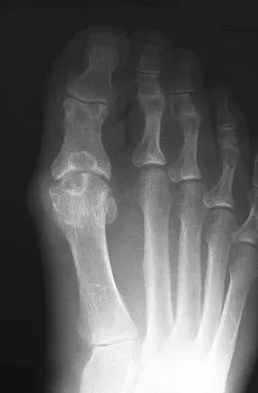

Figure 1 shows the radiograph of an 11-year-old boy who stubbed his great toe while playing soccer barefoot. He is able to walk home despite a small amount of bleeding at the nail fold. Management should consist of

Explanation

Great toe fractures through the physis should be considered open fractures if there is bleeding at the nail fold. Treatment should include irrigation and debridement and appropriate antibiotics. Immobilization with a cast is usually sufficient for treatment of the fracture. Noonan KJ, Saltzman CL, Dietz FR: Open physeal fractures of the distal phalanx of the great toe: A case report. J Bone Joint Surg Am 1994;76:122-125.